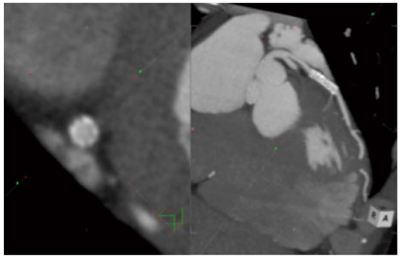

図2 マクロ処理後のSlab MIPビューワ画面

「レイアウト切り替え」「MPR表示」「MIP厚設定」「MIP表示」まで,一連の処理がワンクリックで進んでSlab MIP用の観察画面となる。この状態で長軸面を観察していく。短軸面を観察したい場合は「MPR参照線」ボタンをクリックすれば,長軸面と画像をリンクさせながら短軸面を観察することができる。